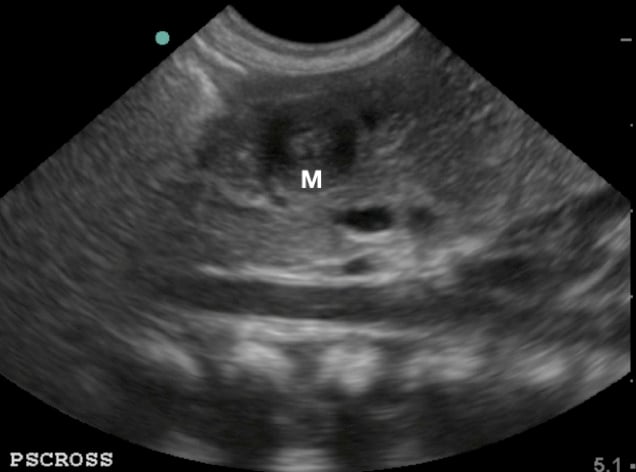

- Figure 3.Sonogaphic anatomy of the pyloric muscle (M) in relation to the aorta (Ao), superior mesenteric artery (SMA), and splenic vein (SV)

- Figure 5. Pylorus in short axis/ transverse view, the “target sign” (M: pylorus muscle)